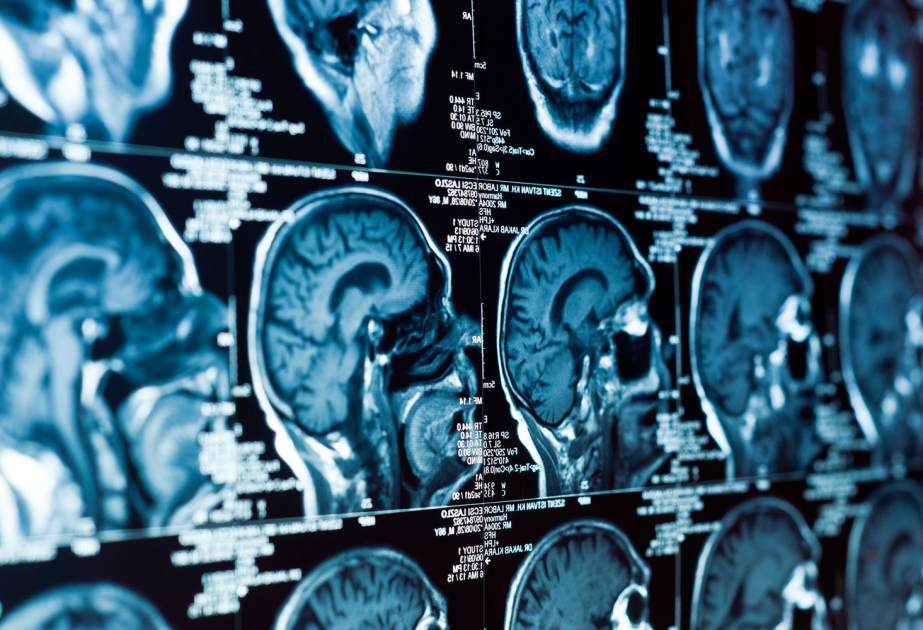

İsveçrənin Sürix və ABŞ-ın Nyu-York universitetlərinin tədqiqatçıları beyin¬də eyni anda bir neçə sahəni yüksək dəqiqliklə ultrasəs vasitəsilə stimullaşdırmağa imkan verən texnologiyanı təqdim ediblər.

İndiyədək ultrasəs neyromodulyasiyası yalnız bir nöqtəyə təsir göstərməyə imkan verirdi və bu da məhdud səmərəliliklə, həmçinin yüksək yan təsir riski ilə müşayiət olunurdu. Yeni cihaz isə yüzlərlə miniatür ötürücüdən ibarətdir. Onların yaratdığı ultrasəs impulsları bir-biri ilə üst-üstə düşərək hologramdakı işıq dalğalarını xatırladır. Nəticədə beyində bir neçə fokus nöqtəsi yaranır və neyron şəbəkələri aktivləşir.

Texnologiya siçanlar üzərində sınaqdan keçirilib. Heyvanlara kəllə sümüyü üzərindən qeyri-invaziv stimulyasiya aparılıb və neyron şəbəkələrinin aktivliyi qeydə alınıb. Alimlərin ehtimalına görə, ultrasəsin təsiri təkcə lokal zəif istiləşmə ilə deyil, həm də neyronların ion kanallarına mexaniki təsirlə bağlıdır.

Hazırda metod fundamental tədqiqat mərhələsindədir, lakin gələcəkdə Altsheymer xəstəliyi, epilepsiya, tremor, Parkinson xəstəliyi və depressiyanın müalicəsində tətbiq oluna bilər.